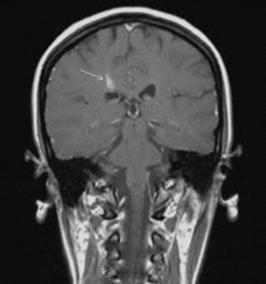

Figure 22.3 Contrast-enhanced coronal MRI showing a contrast-enhancing lesion (arrow) in a patient with relapsing–remitting MS.

Contrast-enhanced T1-weighted imaging

Gadolinium enhancement is used to detect active foci of blood–brain barrier disruption, and therefore active MS (Figure 22.3). Almost 75% of MS lesions will enhance for <1 month, and almost 95% will enhance

for < 2 months.3 It is important to understand, however, that new symptoms may not necessarily correlate with enhancing lesions and that enhancing lesions may not be accompanied by new symptoms.